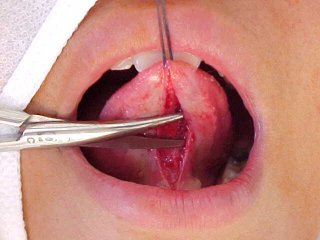

Tratamento cirúrgico da "Língua Presa". Frenectomia ou Frenulotomia Lingual

| Esta técnica cirúrgica destina-se à liberação dos movimentos funcionais da língua . Neste caso a inserção mais anterior se mostra aderida à gengiva: